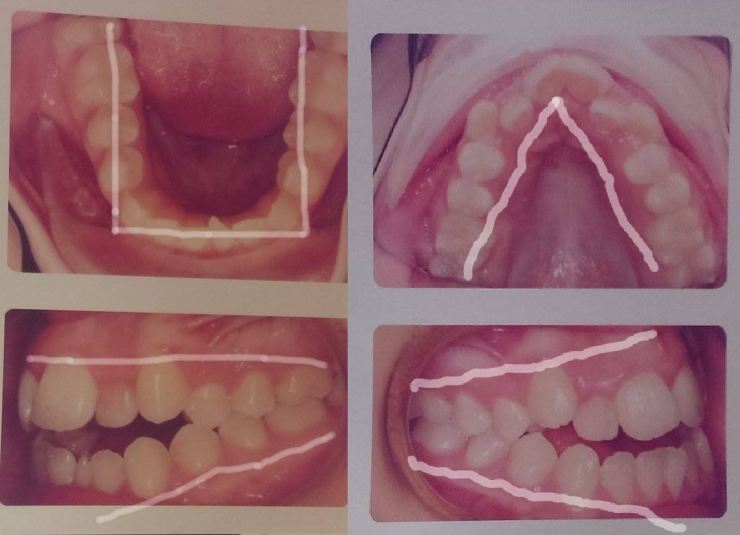

Because her jaw was misshapen, her teeth were not aligned well, and so she had to wear braces. She was insulted by regularly being called a 'monster'. She explains that some other students' parents even looked at her with disgust!

And indeed, with time after surgery, the transformation is impressive.